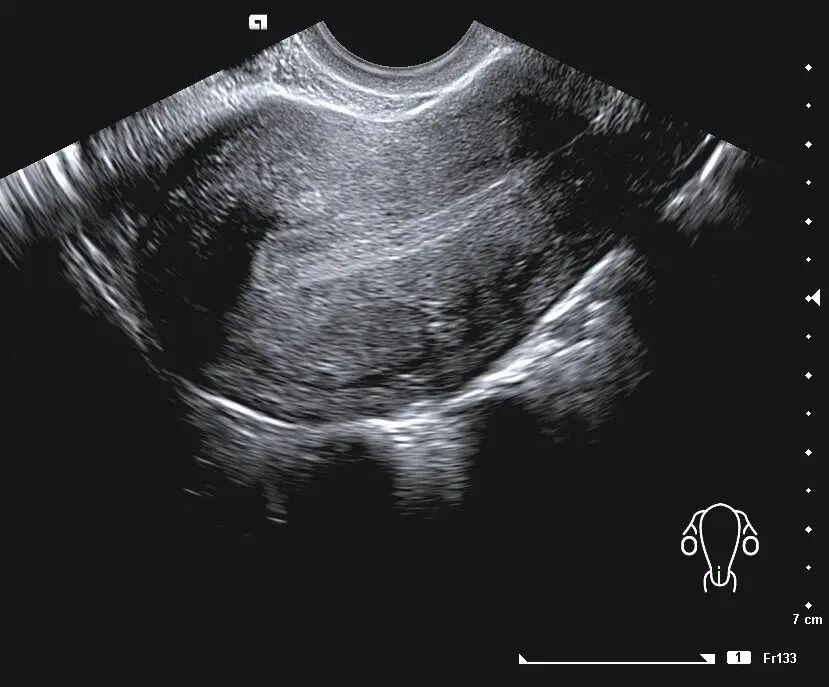

阴道B超是目前临床最常用的评估子宫内膜容受性的无创的方法,可以直接观察到内膜的厚度、类型、容积与血流、蠕动波等。

② 子宫内膜类型

子宫内膜类型分为 A、B、C 3 种。

A型,也就是三线型内膜;

B型,为弱三线型;

C型,均质强回声。

C型,宫腔中线回声模糊

B型,子宫内膜呈现为相对均匀的中等回声内膜,宫腔中线尚清楚

A型,三线呈均质线状的高回声,三线和子宫肌壁及宫内膜的分界比较清楚

取卵日、移植日子宫内膜呈三线征,即A型者,妊娠率显著高于后两者。

目前大多数研究证明, A型子宫内膜临床妊娠率显著高于 B、C型子宫内膜。